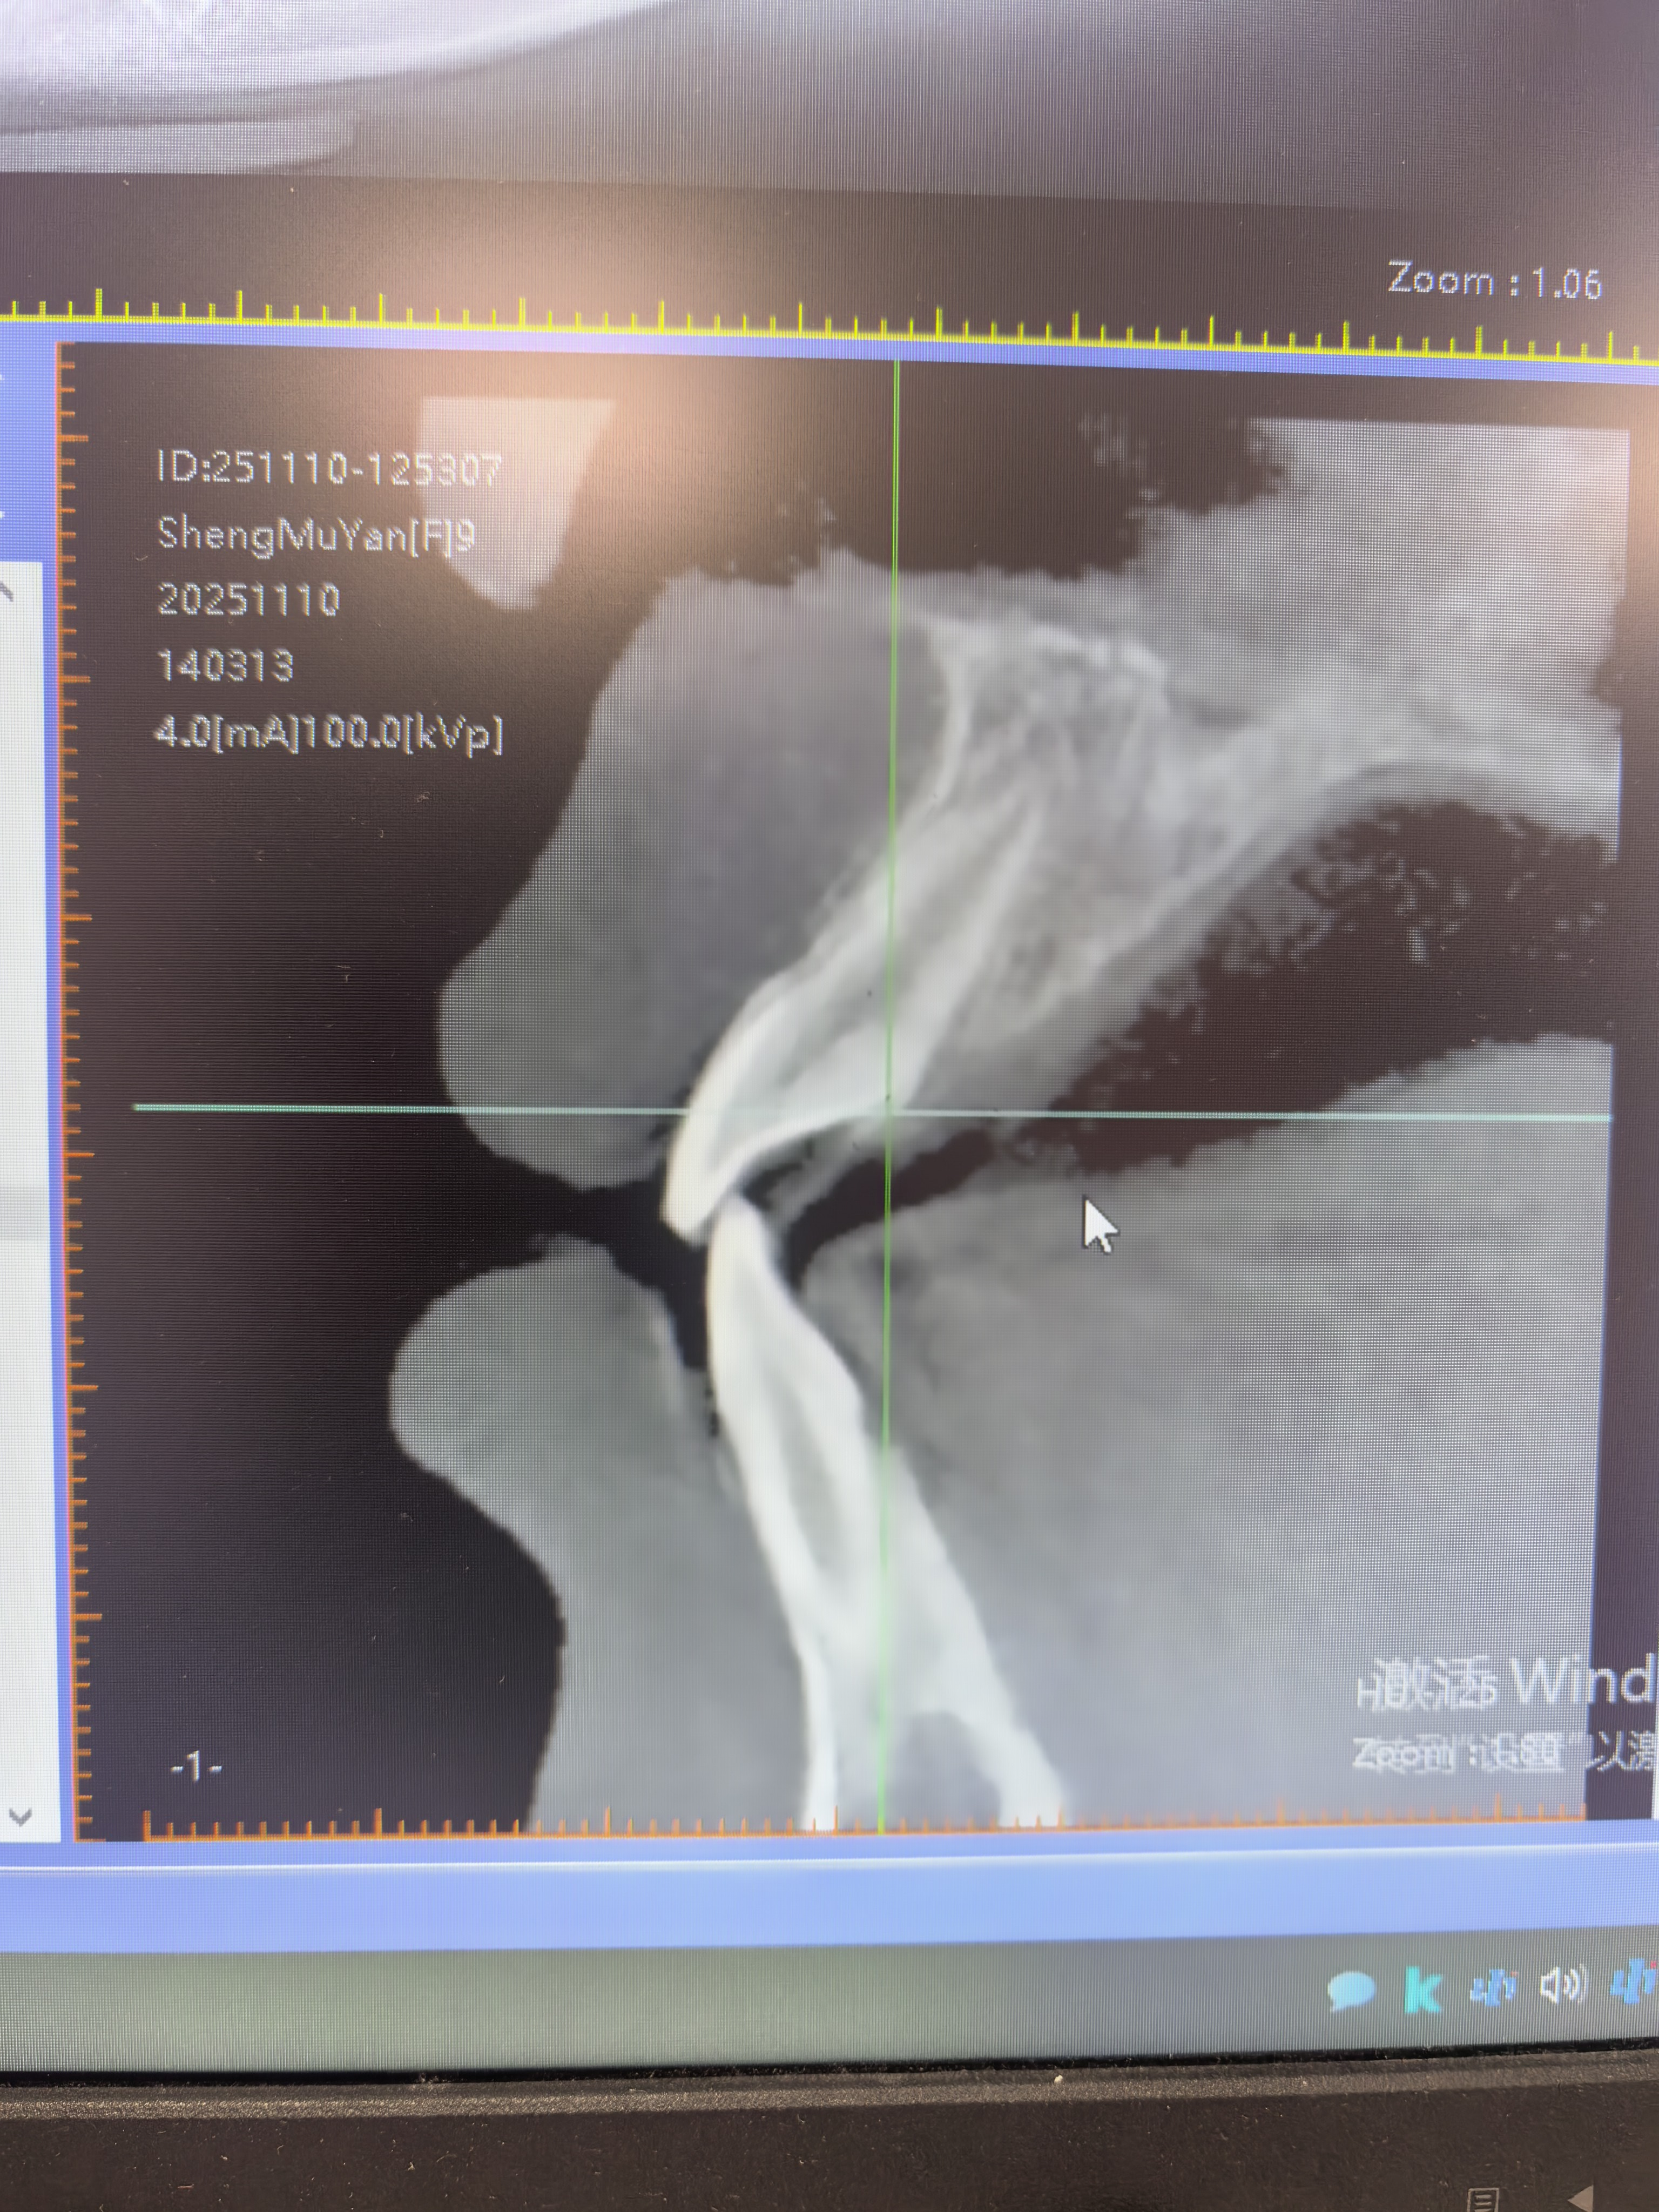

- 咬合回归正常:前牙反合解除,恢复上牙覆盖下牙的健康关系;磨牙关系从三类转为稳定的一类。

- 面型美观蜕变:凹面型转为协调的正常面型,侧颜线条柔和流畅;鼻唇沟区域饱满,恢复了儿童的面部立体感与甜美度。

矫治前 矫治后